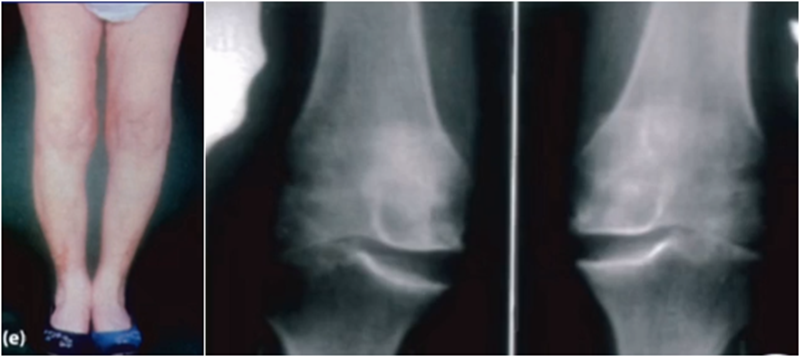

AMOA查体与X线特点,站立位屈曲内翻

外翻应力片可以辅助评价外侧间室关节软骨厚度是否正常,以及内侧副韧带功能是否完整。外侧全层软骨、外侧有骨赘的情况下都不是禁忌证,如外侧出现软骨磨损则为禁忌证。

外翻应力片还可以观察内侧间隙,如内侧副韧带出现挛缩,间隙狭窄,那么此时不适合单髁。

可以矫正畸形,恢复关节间隙和MCL张力

AMOA的X线正位的表现